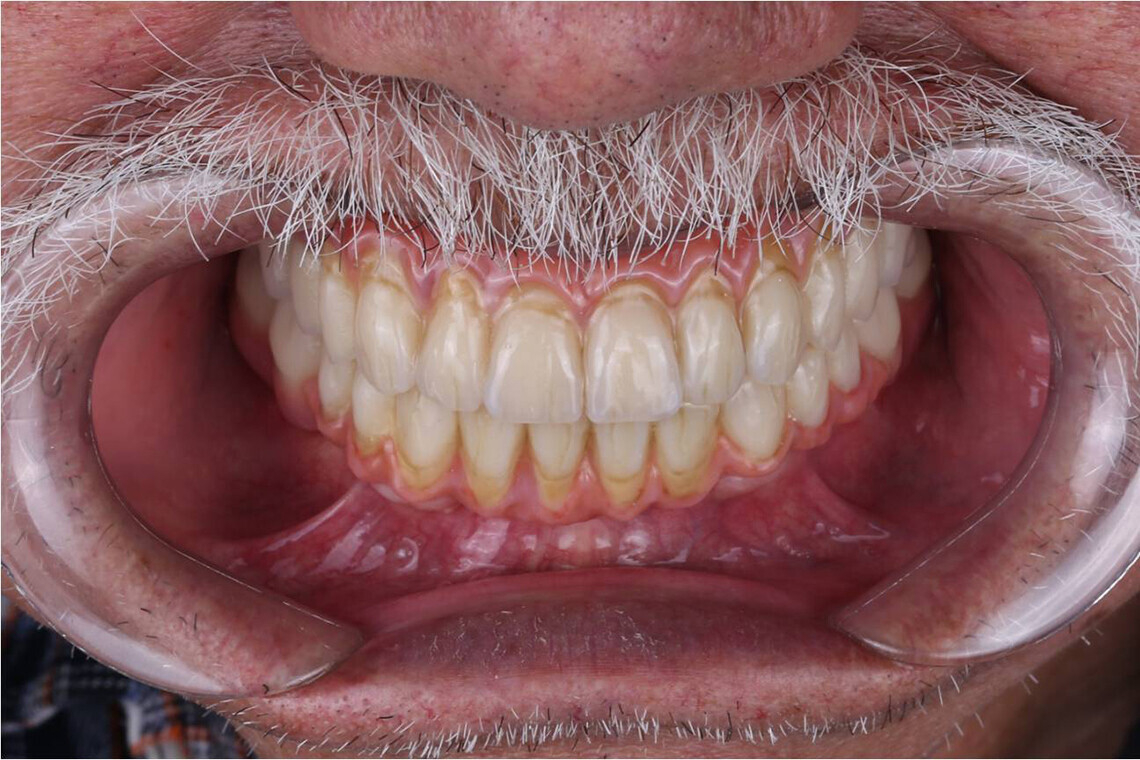

- Высокие эстетические свойства.